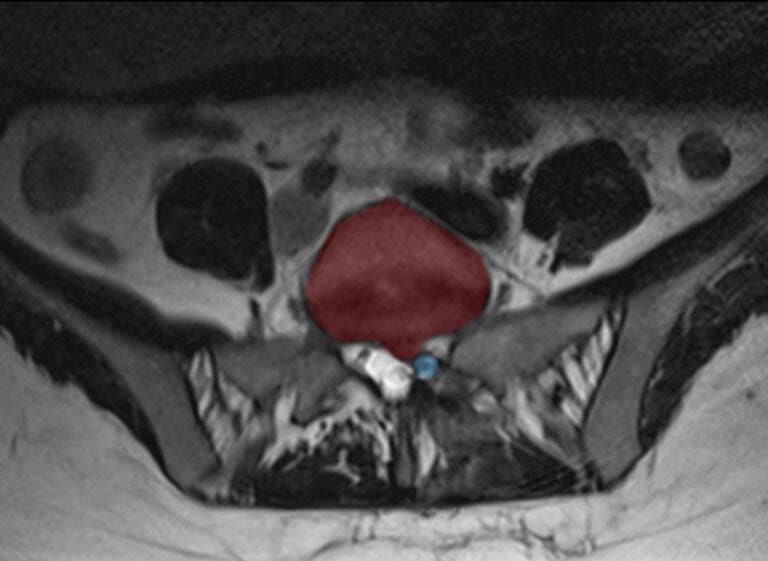

WebLa prise en charge opératoire d’une hernie discale comporte quelques risques à mettre en balance avec le bénéfice chirurgical. Lorsque l’indication est absolue (déficit. WebCes examens permettent d’analyser de façon précise les rapports de la hernie discale avec les structures nerveuses. C’est ce conflit disco-radiculaire qui est responsable de.

Webvue arrière d'un homme souffrant d'une douleur dorsale lombaire aigue ou d'une hernie discale ou d'un lumbago avec l'imagerie de rayon x d'épine dorsale à. WebLa radiographie du rachis lombaire peut être normale ou mettre en évidence des signes de discopathie sous la forme d’une perte de la hauteur discale normale. L’IRM et le scanner. WebLa hernie discale, située entre les vertèbres L4 et L5 (flèche rouge), est en train de pincer le nerf spinal qui s'étend à partir de la moelle épinière, entraînant une pression et une.

WebDans 90 % de cas, les hernies discales surviennent au niveau des vertèbres lombaires (en particulier entre la 4e et la 5e vertèbres lombaires, ou entre la 5e lombaire. WebPuisqu'il est impossible de visionner une hernie discale sur une image radiographique, il est recommandé d'avoir une IRM pour localiser la hernie discale. L' image de la page.